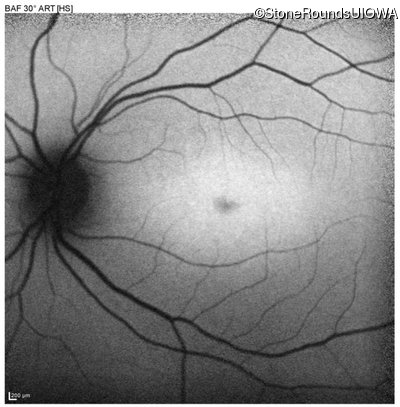

Blue Autofluorescence - Right - 20/125 +1

Exemplar